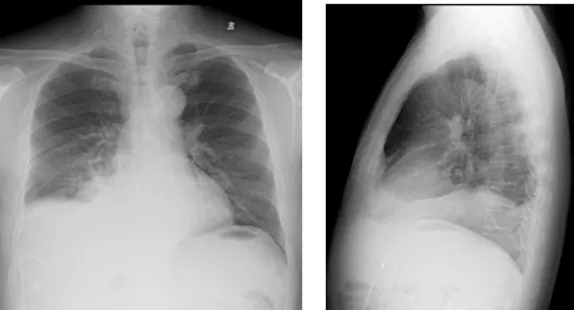

增強CT結(jié)果

image.png

壺腹部腺癌術(shù)后改變,左右肝管匯合部異常信號,不除外復發(fā)可能;考慮肝內(nèi)多發(fā)轉(zhuǎn)移瘤形成

所見右側(cè)胸腔積液,右下肺片狀異常信號,建議進一步胸部檢查